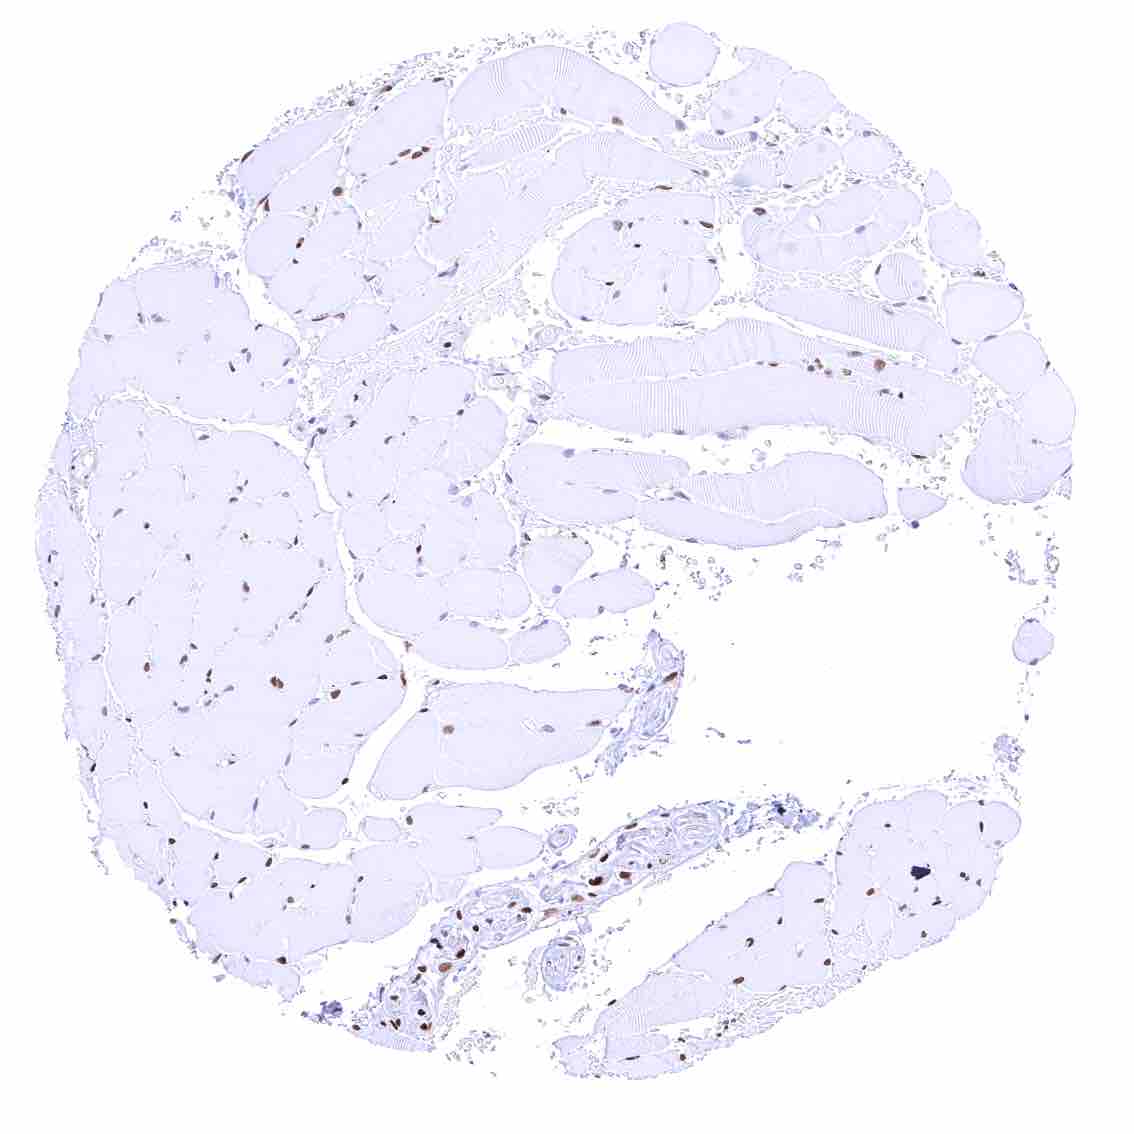

Testis – Weak to moderate nuclear p27 staining of a subset of cells (predominantly Sertoli cells).